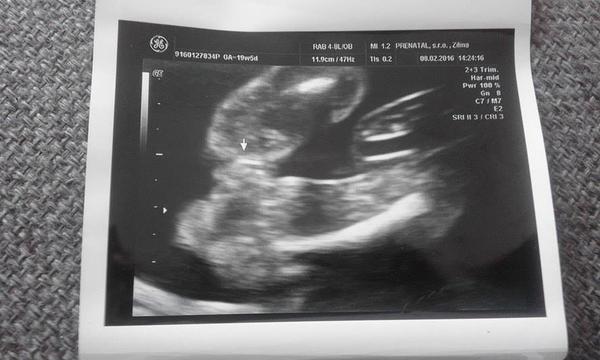

Pomýlil sa doktor pri určení pohlavia na 3D sone v 20 týždni?

no neviem baby ci ste si vsimli, ale za poslednu dobu, dost kratky cas, som sa stretla uz s niekolkymi pripadmi, ked lekari urcili pohlavie na 3D na 100% a nakoniec sa pomylili...

caute baby, ono je to take diskutabilne. poznam rodinku, ktorej celu dobu hovorili, ze to bude chlapec a narodilo sa dievcatko, mojej svagrinke naznacovali dievcatko a je z toho maly Risko 🙂 ale podla mna, ak to potvrdi viac sono, tak je to istejsie🙂

nam v 19 tt povedal lekar, ze to bude chlapec, ze vidno gulky a tie gulky sa nemaju s cim pomylit, ale ties je to vraj na 90%. No vsak uvidime, ci sa to nezmeni, za tyzden idem na dalsie sono to budem v 22tt, tak dufam, ze sa to uz nezmeni, lebo uz som niake vecicky nakupila